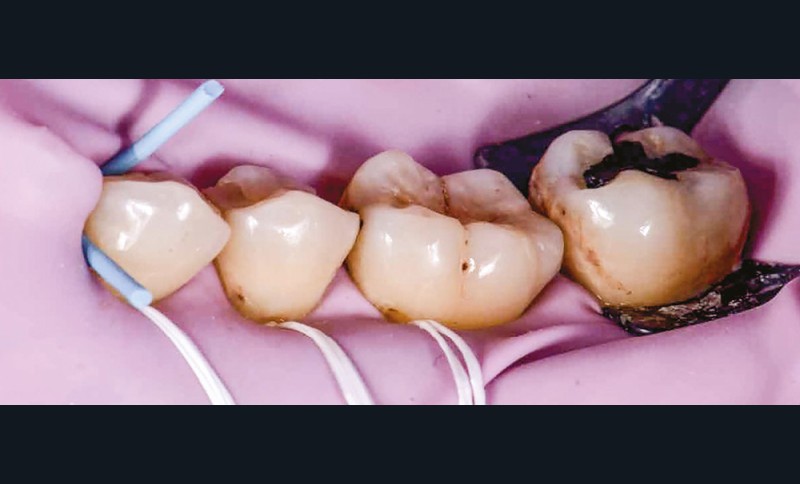

La première anesthésie se situe au niveau de la papille proximale entre 35 et 36. L’aiguille blanche de diamètre 0,30 mm et de longueur 16 mm est orientée de façon à avoir son repère légèrement décalé de la fenêtre du porte-aiguille (fig. 4). Ainsi, le biseau se pose à plat contre la muqueuse [1]. L’aiguille glisse doucement et de façon indolore dans la papille sur 2 mm et l’injection débute sans surpression sous contrôle électronique. Lorsque la papille montre une vasoconstriction suffisante, elle devient blanche et l’injection peut s’arrêter. La pièce à main s’oriente alors en direction de l’espace apical interdentaire avec un angle de 30 à 45° vestibulolingual (fig. 5). L’aiguille est mise en rotation pour pénétrer la corticale osseuse. Elle arrive ensuite dans la partie trabéculaire de l’os. Lorsque les deux tiers de l’aiguille sont sous la corticale, la rotation doit cesser et l’injection reprend avec une vitesse qui s’adapte électroniquement à la densité de l’os. Une demi-carpule d’articaïne 1/100 000 suffira à la restauration de ce secteur [2]. Le champ opératoire, le crampon, les ligatures sont placés (fig. 6) ; un crampon additionnel permet de descendre la ligature dans le sulcus de la 36 pour réaliser le soin vestibulaire (fig. 7). Les restaurations sont réalisées sans douleur (fig. 8) [3].